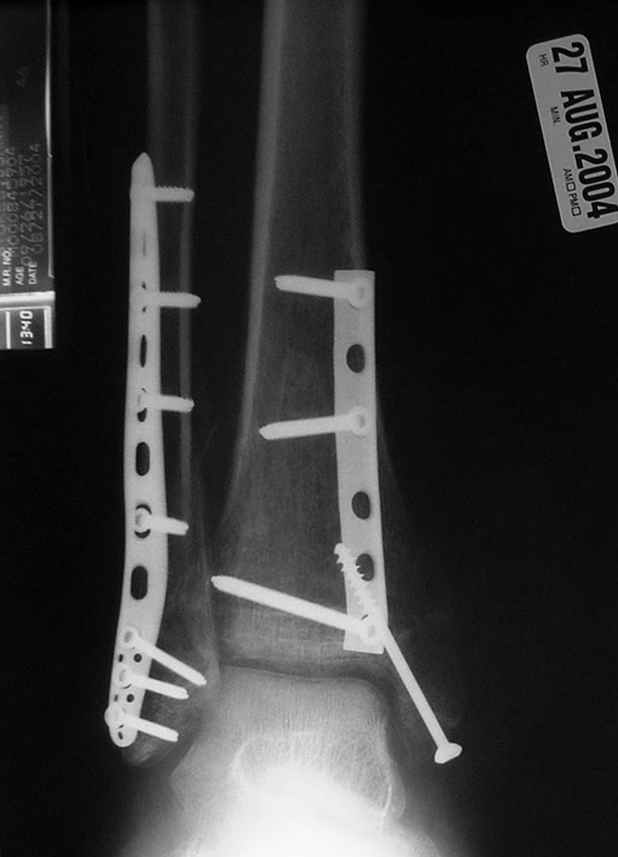

Dear all,40 y.o. man had sustained this terrible fracture falling from a motorbike.

Closed fracture.

We have put his limb in traction.

After some days of traction I would like to insert an external fixator (I think a circular one instead of a monoaxial one, because of the multiplanar situation of the fracture).

This is really Pilon Fx (C3.3; the high energy and the extent of distal tibia comminution are defining it).